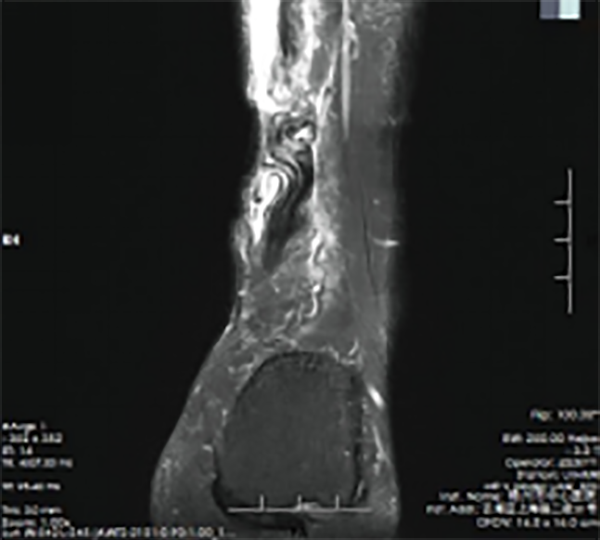

近日,我院骨外一科再次完成一例“跟腱斷裂微創(chuàng)縫合手術(shù)”,為運(yùn)動(dòng)性損傷的病人提供了堅(jiān)實(shí)的醫(yī)療保障?;颊咴谟鹈蜻\(yùn)動(dòng)中突感小腿砰的一響,當(dāng)即出現(xiàn)足跟部疼痛,活動(dòng)受限。被家人送至我院就診。

專(zhuān)科查體與核磁影像結(jié)果相符,確診為左側(cè)跟腱斷裂。